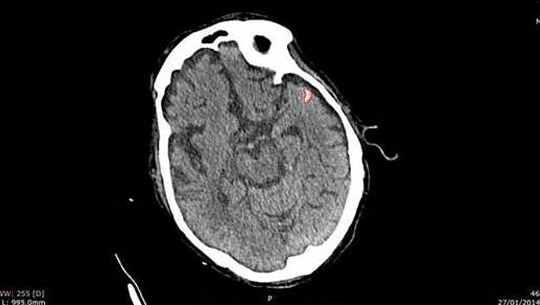

Imagen de la evaluación de MedyMatch de Israel del accidente cerebrovascular. (Cortesía)

El software desarrollado por la nueva empresa basada en Tel Aviv, basado en el aprendizaje profundo y la inteligencia artificial, puede analizar automáticamente imágenes de tomografías computarizadas sin contraste, que son las exploraciones estándar utilizadas para la evaluación inicial de posibles hemorragias intracraneales en hospitales y salas de emergencia. Usando algoritmos, el software puede identificar y alertar a los médicos sobre la presencia de ICH en estos escaneos. Esto permite a los médicos determinar rápidamente si hay una hemorragia o no; el tiempo es esencial porque durante cada minuto que pasa, las células cerebrales mueren.

Los productos incluirán aplicaciones que leen imágenes de TC y ayudan a los médicos a priorizar los casos de acuerdo con la gravedad, y aquellos que «proporcionan una segunda lectura», rodeando áreas que podrían tener una hemorragia intracraneal, dijo Saragnese.